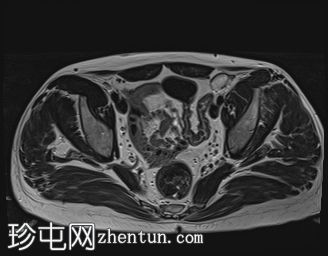

MRI

左侧阴囊空虚。

左侧睾丸位于盆腔左侧前壁,腹股沟管上方。其体积较小(与对侧正常的右侧睾丸相比)。T2加权像呈高信号,T1加权像呈低信号,未见明显局灶

性病

变。

右侧睾丸位于右侧阴囊内,大小和形状正常。